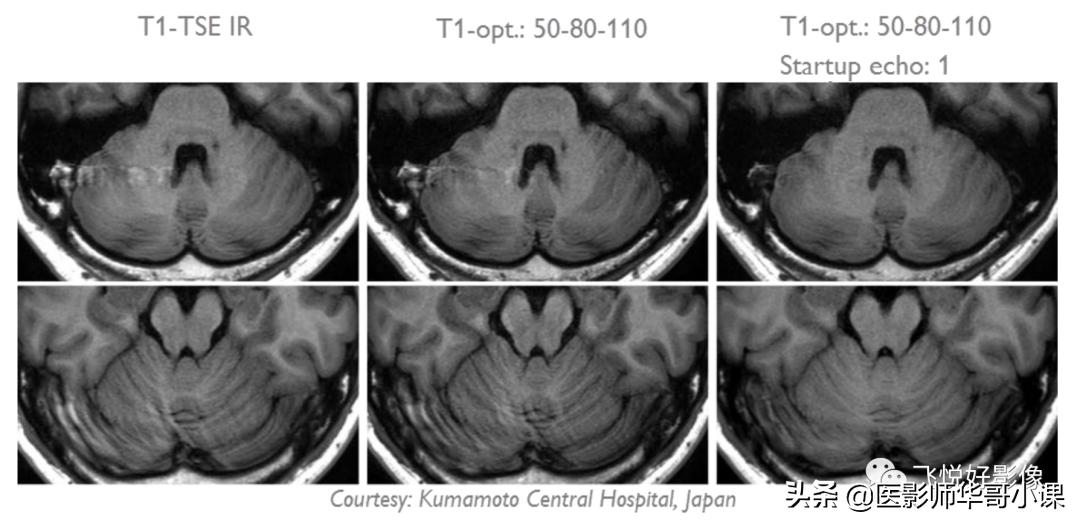

图12.PSS在头颅的应用,使用PSS血管搏动伪影减少

- 对于T1加权图像,使用"T1-optimized"选项:a. 只适用于2D, MS和M2D;b. 如果有截断伪影,可以尝试加一个startup echo;c. "min. angle"和"max. angle"之差太大(~40°)可能导致图像模糊;d. 减小"min. angle"可以提高T1权重,同时可以减少运动伪影;e. 增大"max. angle"可以提高SNR,但是同时也会增大SAR。